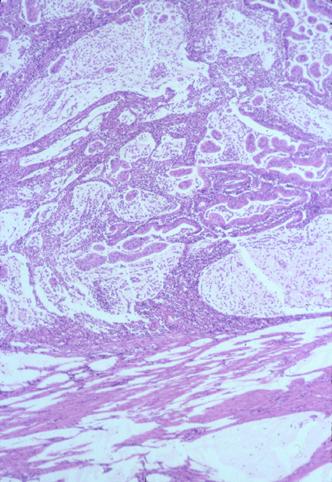

疾患(病理主体)の分類悪性上皮性腫瘍/腺癌

部位(臓器別)大腸/虫垂

検査方法ミクロ

腫瘍の肉眼分類2型(潰瘍限局型)/

病変の最大径(ミリ)25〜29

腫瘍の深達度s(a)